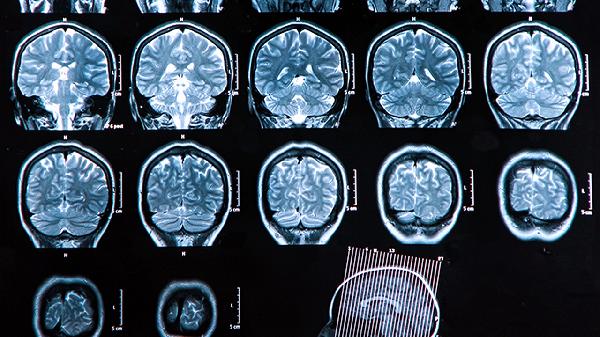

大脑神经元异常放电会引起意识丧失伴肢体抽搐,常见于癫痫大发作。发作时可能伴随口吐白沫、尿失禁等症状。需长期服用丙戊酸钠、卡马西平等抗癫痫药物控制,避免驾驶、游泳等高风险活动。首次发作需完善脑电图和头颅影像学检查。

头部受到外力撞击可能导致脑震荡或颅内出血,出现意识障碍。轻者表现为短暂昏迷后清醒,重者持续昏迷伴呕吐、瞳孔不等大。需立即进行头颅CT检查,硬膜下血肿等需手术清除血肿。康复期可能出现头痛、记忆力减退等后遗症。